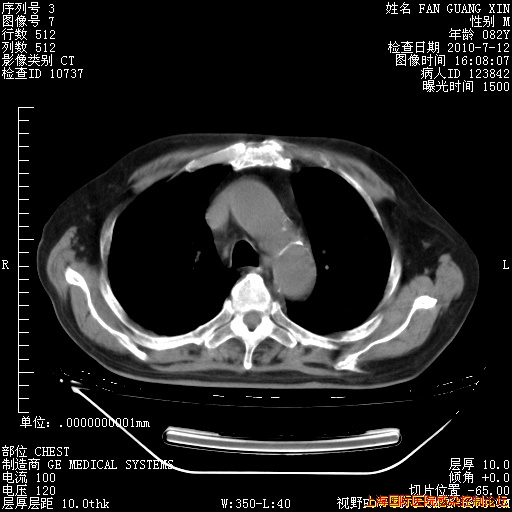

6月12日纵膈窗

今天复查CT

今天CT

整整相隔30天的肺部CT好像有所好转啊。甲强龙减量第3天,需要观察体温。

海管,自昨日你和我通完话后,不知您岳父消化道症状有无缓解?体温怎样?阅读7.12日胸部ct,个人认为目前激素治疗是有效的,甲强龙减量是适宜的。因在抗痨治疗,需密切观察肝功、肾功能和血常规。不过,老年、长期住院和大量使用激素,很担心菌群失调发生